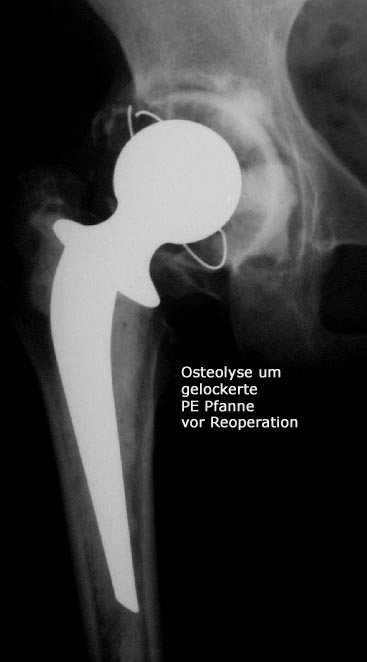

Reoperationen von gelockerten Gelenksprothesen

Reoperationen von gelockerten Gelenksprothesen sind anspruchsvolle operative Eingriffe , bei denen die Erfahrung des Operateurs und die Gabe zur richtigen Einschätzung der optimalen Versorgungsform von grosser Bedeutung ist. Reoperationen können dann erforderlich werden, wenn das Gefüge zwischen Knochen und Prothese aufgelockert wird – so kann eine Entzündung, ein vermehrter Abrieb der Prothesenteile, ein Bruch des die Prothese umgebenden Knochens aber auch Verletzungen der Weichteile eine Prothesenlockerung verursachen. Rasches Handeln ist dann angezeigt wenn der Patient über Schmerzen klagt, Röntgenuntersuchungen die Änderung der Prothesenposition

erkennen lassen oder Spezialuntersuchungen wie zum Beispiel eine Szintigraphie Hinweis auf eine Prothesenlockerung geben. Der operative Eingriff selbst ist für den Patienten belastend aber nur durch rasches Handeln kann die weitere Zerstörung von Knochen und Weichteilen verhindert werden.